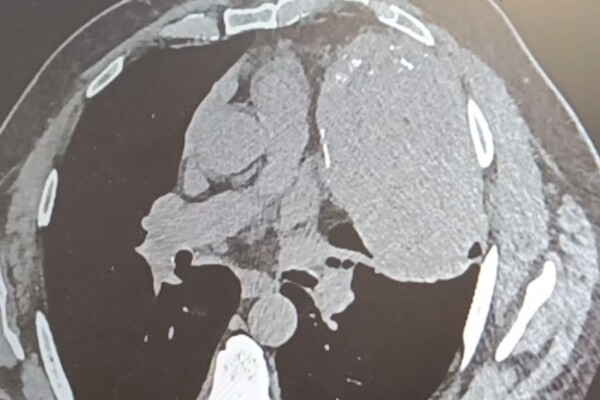

Снимок внутренних органов. Источник: Минздрав Оренбургской области В Оренбурге врачи удалили огромное новообразование в грудной клетке у жителя Орска, которое начало формироваться между сердцем,

В Оренбурге врачи удалили огромное  новообразование в грудной клетке у жителя Орска, которое начало формироваться между сердцем, правым легким и ребрами около 20 лет назад.

Ранее новообразование не мешало пациенту, поделились в Минздраве. Со временем оно сильно увеличилось, заполнило пространство в грудной клетке и стало сдавливать легкое. Усугубилась ситуация в 2024 году, когда мужчина заболел пневмонией. Его направили в ООКБ №2, чтобы сделать операцию.

Продлилась операция почти 3 часа. Работу осложняло близость новообразования к крупнейшим кровеносным сосудам и сердцу. Однако хирурги со своей задачей справились успешно.